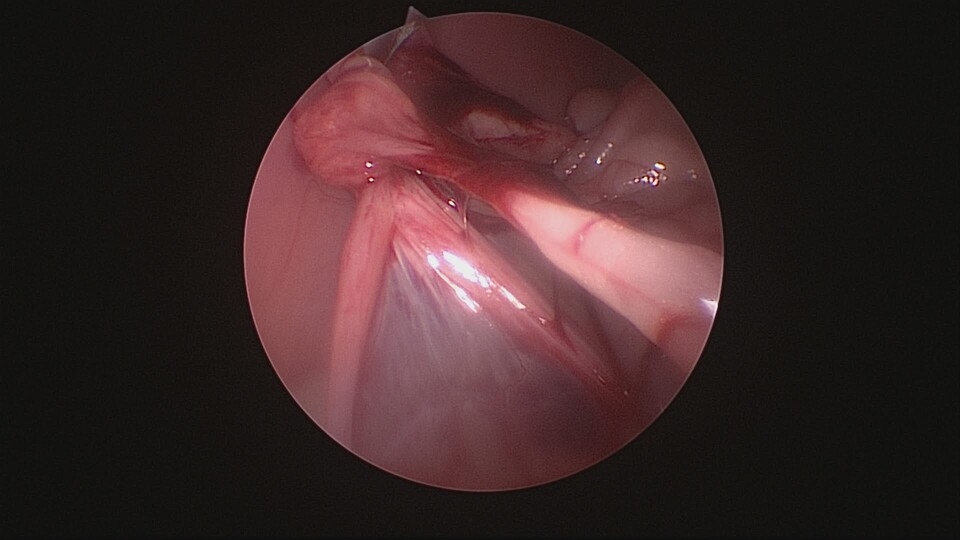

1. 傷口要小喔 (手術視野範圍越小,越不容易看清楚臟器的全貌,部分卵巢殘留或術中出血狀況也不易被察覺。追求傷口小可考慮內視鏡手術)

卵巢殘留症候群是指在進行卵巢子宮切除術(OHE)後,卻因卵巢組織未完全切除,導致體內仍有部分卵巢組織殘留,進而分泌性激素,引發類似發情的症狀。常見於狗與貓,可能會出現陰道分泌物、行為改變、乳腺腫脹等現象。

*卵巢組織切除不完全

*解剖位置異常導致遺漏

*手術視野不佳或操作困難

*腹腔沾黏使卵巢不易辨認